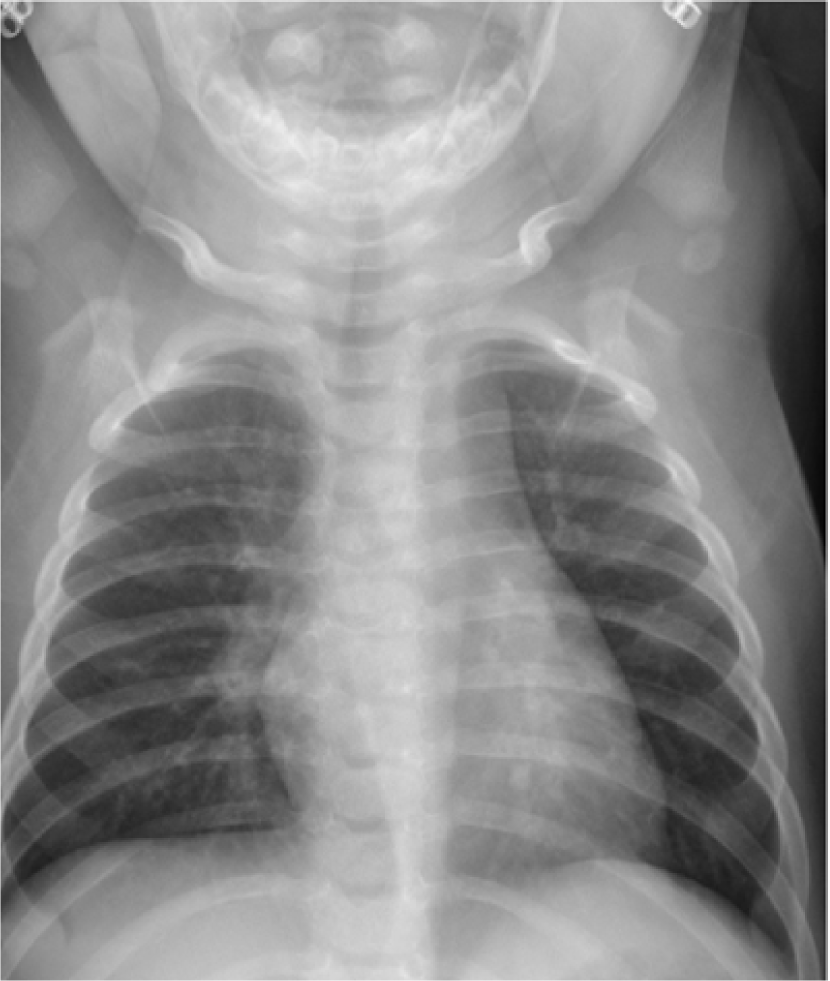

Despite tremendous advancements in tomographic imaging, chest radiography remains the most commonly used imaging modality for pulmonary analysis mainly due to its low cost, low radiation dosage, and widespread availability. Radiation dosage is of particular concern in pediatric applications, especially in neonatal intensive care units where chest radiographs (CXRs) are considered the first option for pulmonary diagnosis [1]. Lung field segmentation is the necessary initial step for image-based pulmonary analysis. Accurate delineation of lung field from CXR, however, is challenging due to ambiguous boundaries, pathologies, occultation of lung field by anatomical structures in thorax, anatomical variation of lung shapes, and size across subjects (Fig. 1). Part of the challenge in developing computer-aided diagnosis (CAD) methods, especially for pediatric cohorts, is also the anatomical shape variation of lung field that occur during growth [2, 3]. As shown in Fig. 1, pediatric cohorts have a more compliant chest wall, small thoracic cage, and relative large abdominal space. Furthermore, the diaphragm of children has smaller apposition area which has a concave shape in the posterior-anterior (PA) view CXR [3]. Therefore, existing approaches to lung field segmentation that are designed primarily for adult cohorts, are not accurate at analyzing the pediatric subjects. Although a few pilot studies such as [2] have been conducted recently to look at the age-related radiological biomarkers in lungs, no comprehensive study of pediatric lung field segmentation exists to the best of our knowledge.